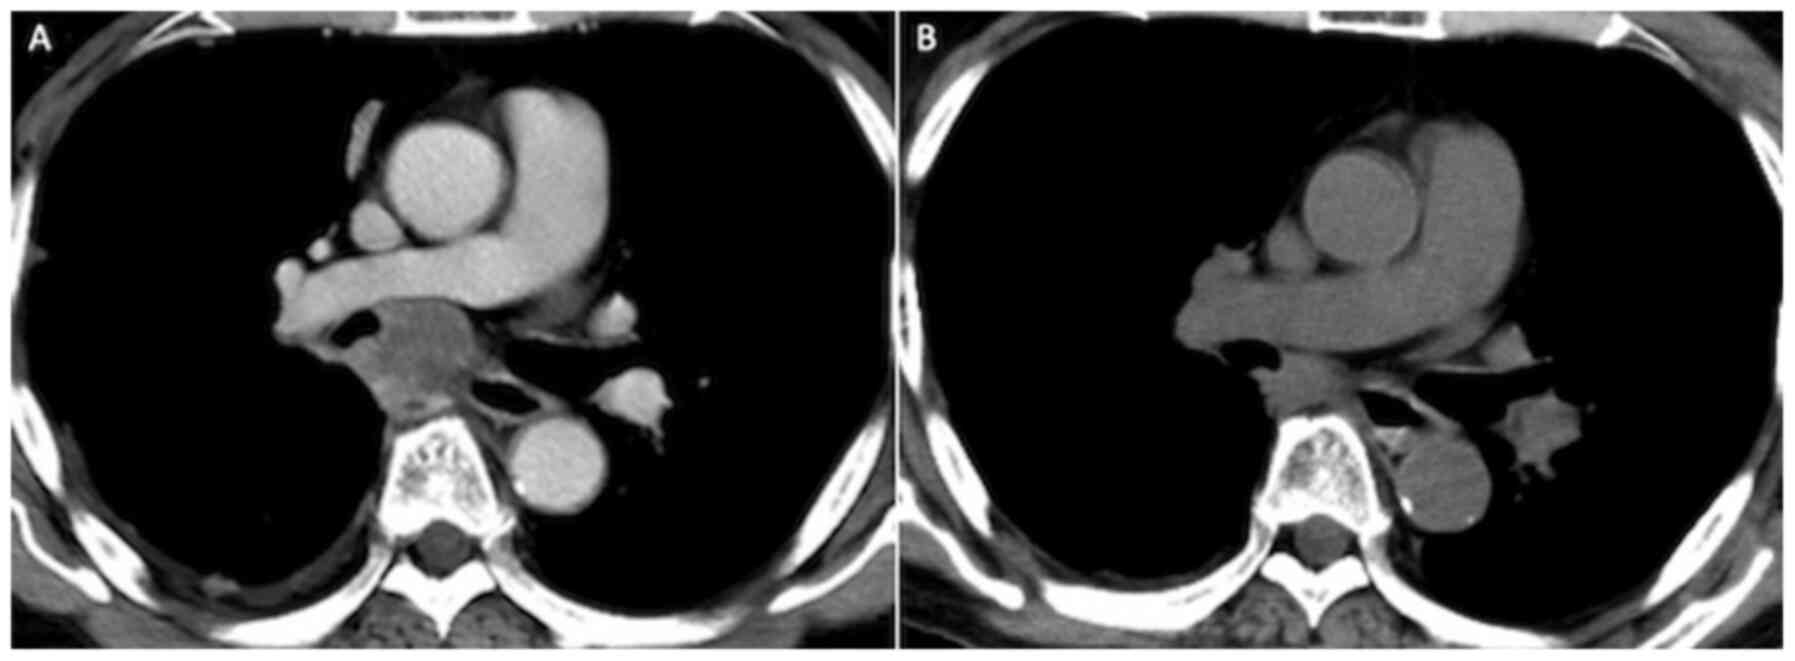

Figure 4

CT findings. (A) CT prior to pembrolizumab treatment. (B) CT 56 days after treatment showed tumor shrinking and partial response, based on the response evaluation criteria in solid tumors. CT, computed tomography.